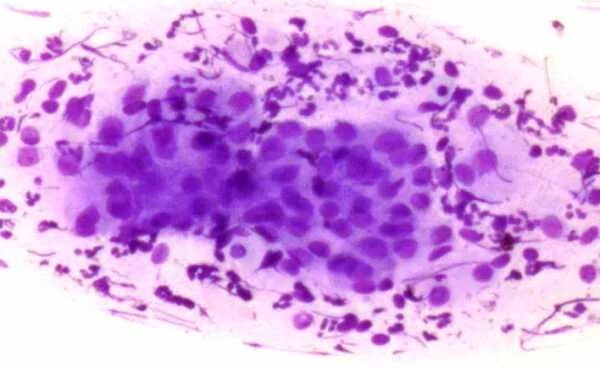

Дегенеративные изменения цитограмма